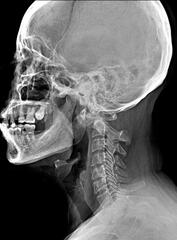

Conducto cervical estrecho